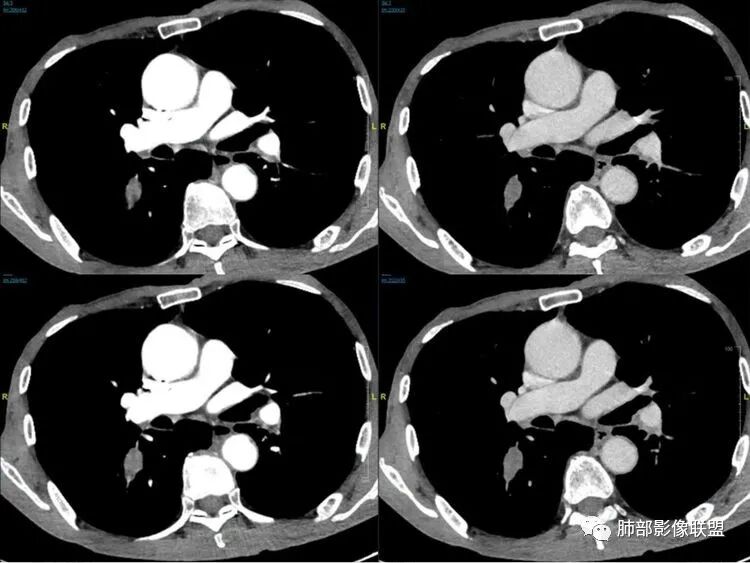

老年男性患者,胸部隐痛1月入院,有长期吸烟史,胸部CT:右肺下叶背段梭型结节灶,边界清晰,无明显分叶、毛刺及周边磨玻璃影,内部密度不均匀,支气管截断,增强扫描不均匀轻度强化,内部似乎见支气管黏液栓,纵隔淋巴结不大,考虑恶性病变:小细胞癌(缺少典型的纵隔肺门淋巴结增大融合),鳞癌(病史复合,但没有阻塞性肺炎,内部没有坏死,),类癌(多见于女性患者,与吸烟关系不大),首先考虑典型类癌,

老年男性,右肺下叶梭形或椭圆形结节,形态较规则,边缘光整,支气管截断,增强不均匀轻度强化,右肺门及纵隔淋巴结增大,考虑恶性病变,鳞癌或小细胞癌,神经内分泌癌(小细胞形)。

老年男性患者,右肺下叶背段梭形结节影,边界比较光整,密度均匀,没有明显的分叶毛刺,没有阻塞性肺炎的表现,这些感觉具备有良性的特点。而近端支气管截断,增强明显的强化,纵隔多发的淋巴结,显得是恶性的特点。总体印象,老年患者+支气管截断征象+明显强化的结节+纵隔多发淋巴结,还是考虑恶性结节,小细胞癌或是鳞癌。

男性,老年人,长期吸烟史,老慢支背景,右下肺背段占位,支气管亚段门口堵,病灶长轴与支气管平行,推测腔内生长可能,病灶内血管穿行,周围干净,轻度强化,右肺门淋巴结肿大,考虑恶性,神经内分泌癌(大小类)>淋巴上皮瘤样癌>腺癌>鳞癌

右肺下叶梭形实性结节,密度均匀,边缘光整,局部膨隆,近端支气管截断,轻度强化,血管走行自然,右肺门及纵隔淋巴结增大,考虑小细胞癌>鳞癌

右肺下叶背段结节,沿着支气管走行呈长椭圆形,边缘圆滑清晰,近端支气管阻塞,远端支气管有沿壁增厚,右肺门淋巴结肿大,中度强化,老年男性,吸烟病史,肺气肿背景,考虑小细胞肺癌,鉴别鳞癌

老年男性,吸烟史,右肺下叶梭形肿块,边缘平直有分叶,支气管近端阻塞,右肺门肿大淋巴结,增强后轻度强化,欠均匀,首先考虑恶性,小细胞肺癌?

老年男性+吸烟+右下肺肿块影+支气管截断+淋巴结肿大,考虑恶性,倾向小

老年男性,吸烟史,右肺下叶背段梭型软组织肿块,边缘膨隆,不均匀强化,近端支气管截断,同侧肺门及纵隔淋巴结肿大,支持恶性,小细胞可能大,鳞癌缺少阻塞性改变

晨读,右下叶梭形占位,边界光滑,支气管截断,可见尾征,不均匀轻度强化,肺门淋巴结肿大,有吸烟史,高龄高危患者,首先考虑恶性,考虑小细胞癌,鉴别一下鳞癌

老年男性,前胸隐痛1月。2年前有白内障手术史。右下肺结节,沿中轴呈梭形,膨隆,边清、无分叶,无毛刺,近端支气管截断完全堵塞,病灶以远未见阻塞性炎症及肺不张。内部密度基本均匀,增强轻微强化,似见局部低密度影。纵隔及右肺门见肿大淋巴结。整体考虑恶性可能性大,小细胞癌?鳞癌?注意鉴别良性结节—错构瘤。

老年男性,长期吸烟史,右肺下叶背段梭形低密度灶,边界清晰,无明显分叶、毛刺,边缘稍彭隆,支气管截断,右肺门淋巴结增大,增强扫描不均匀轻度强化(延迟略明显),首先考虑恶性,小?不典型结核球待排。

右肺下叶背段结节,气管堵塞,密度均匀,边界清晰,无明显分叶、毛刺,边缘膨隆,右肺门淋巴结增大,增强轻度强化,考虑小细胞癌,鉴别鳞癌。

右肺下叶梭形软组织结节,密度均匀,明显尾巴,边缘光整,近端支气管截断,轻度强化,血管走行自然,又腊肠尾巴征象

考虑恶性  小细胞癌?

男,83,前胸部隐痛不适1月。有长年大量吸烟史。胸部CT:肺气肿,右肺下叶纺锤型实性结节灶,边界清晰,支气管截断,内部密度不均匀,增强扫描不均匀强化,右肺门淋巴结大。考虑恶性病变:小?鳞?鉴别炎性肉芽肿、错构瘤等。

晨读:老年男性+吸烟+右肺下叶与气管长轴一致的梭形肿块影+支气管截断,轻度强化,右肺门肿大淋巴结,考虑恶性,小细胞肺癌可能,鉴别鳞癌